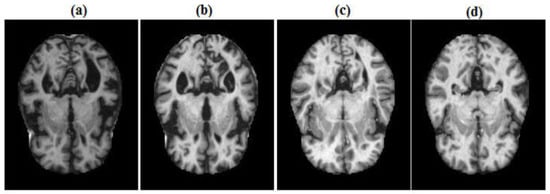

- Preprocessing: MRI scans are aligned to a standard template, resampled for consistency, and segmented into distinct tissue types (gray matter, white matter, and cerebrospinal fluid) to ensure reliable comparisons across subjects.

3.1.2. Preprocessing